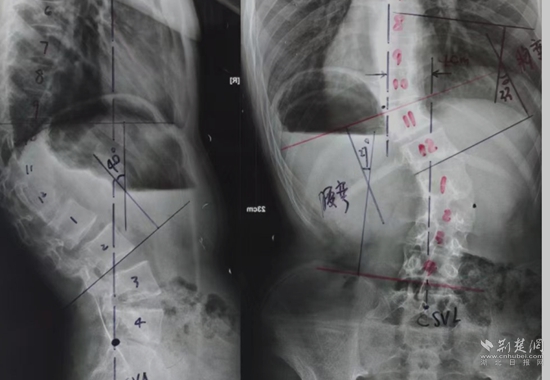

全脊柱X光檢查。通訊員 供圖

余國慶醫(yī)生檢查后發(fā)現(xiàn),這名患者全身皮膚長滿咖啡色的斑塊和瘤狀的突起,身體極為消瘦,骨架突出后可以看到明顯的駝背、剃刀背及側(cè)彎畸形。結(jié)合隨后的全脊柱X光檢查,確診這是一例少見的神經(jīng)纖維瘤病性脊柱側(cè)后凸畸形患者。余醫(yī)生當(dāng)即將這名患者收住院治療。